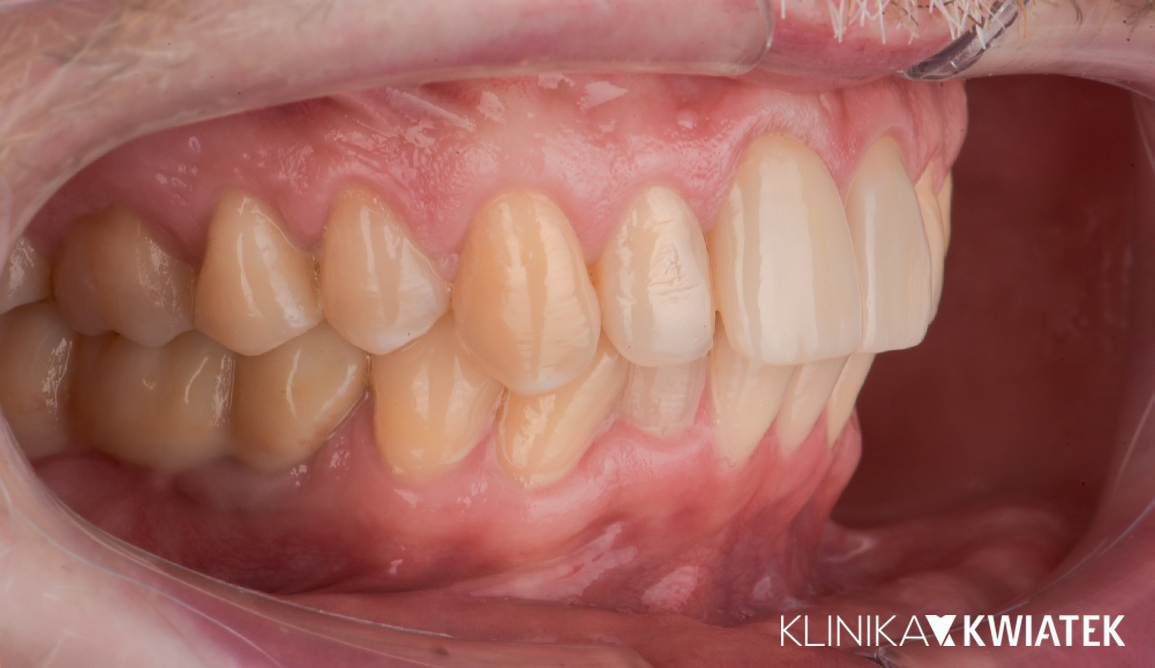

PRZED

PO